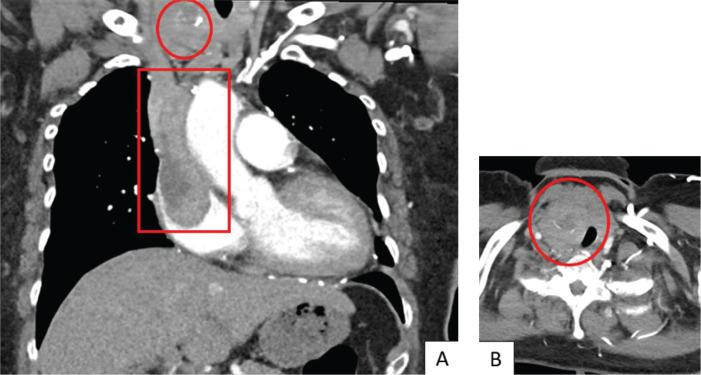

我们报告了一例67岁女性罕见的同步性乳头状甲状腺癌(PTC)和滤泡状甲状腺癌(FTC)的侵袭性病例,该患者最初因格雷夫斯病出现甲状腺毒症。她被发现有两个甲状腺结节,伴有广泛的心脏内肿瘤血栓、有症状的左骨盆骨转移伴病理性骨折、肺转移和纵隔淋巴结转移。进一步检查提示诊断为同步性乳头状和转移性滤泡状甲状腺癌。建议采用根治性手术,随后进行辅助性放射性碘消融治疗,但患者拒绝了所有形式的癌症特异性治疗,仅选择姑息性治疗方法。我们讨论了诊断同步性甲状腺恶性肿瘤时的诊断要点——在本病例中,PTC的明显特征以及由于侵袭性和转移性滤泡病变导致FTC的高可能性。该病例强调了美国放射学会甲状腺影像报告和数据系统(ACR TI-RADS)的潜在局限性,特别是某些提示恶性的超声特征可能未被充分捕捉。值得注意的是,本病例中分化型甲状腺癌的侵袭性表现可能与格雷夫斯病的并存有关,这表明在评估此类患者的潜在甲状腺恶性肿瘤时需要提高警惕。